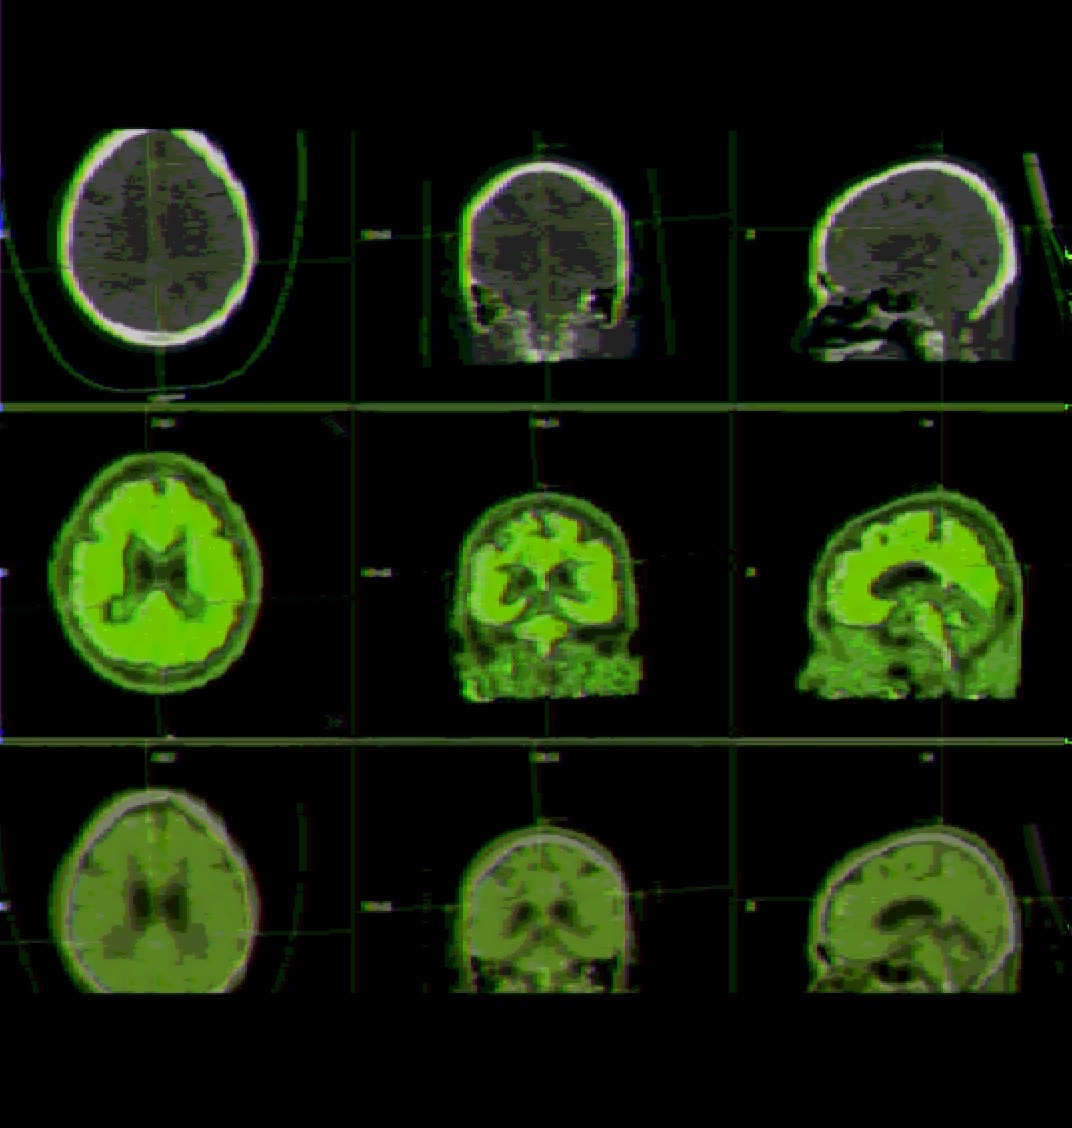

Brain data has been collected. Images of my fMRI, MRI and EEG are pictured above.

Data will be fed into training data of the AI, as well as used as a base brain. In layman's terms, the AI will build itself upon the simulated scaffolding of my brain.